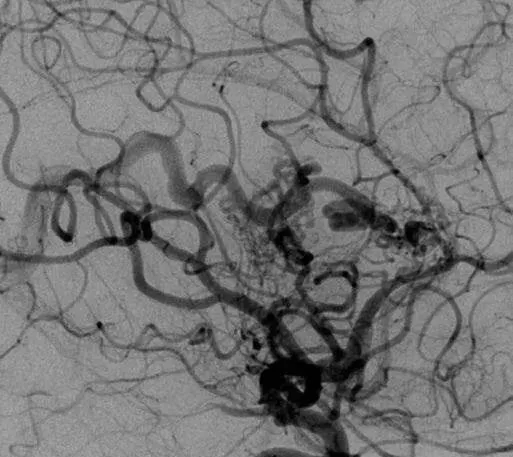

遗传性出血性毛细血管扩张症(HHT)是一类罕见病,却给患者带来长期挑战,除反复鼻出血、皮肤黏膜毛细血管扩张外,脑动静脉畸形(脑AVM)是其更危险且常见的并发症。 由于HHT本身罕见,...

INC国际儿童脑瘤大咖、世界小儿神经系统知名杂志《Childs Nervous System》现任主编Concezio Di Rocco教授发表研究《Angioarchitectural features of brain arteriovenous malformations associated with seizures:a single center re...